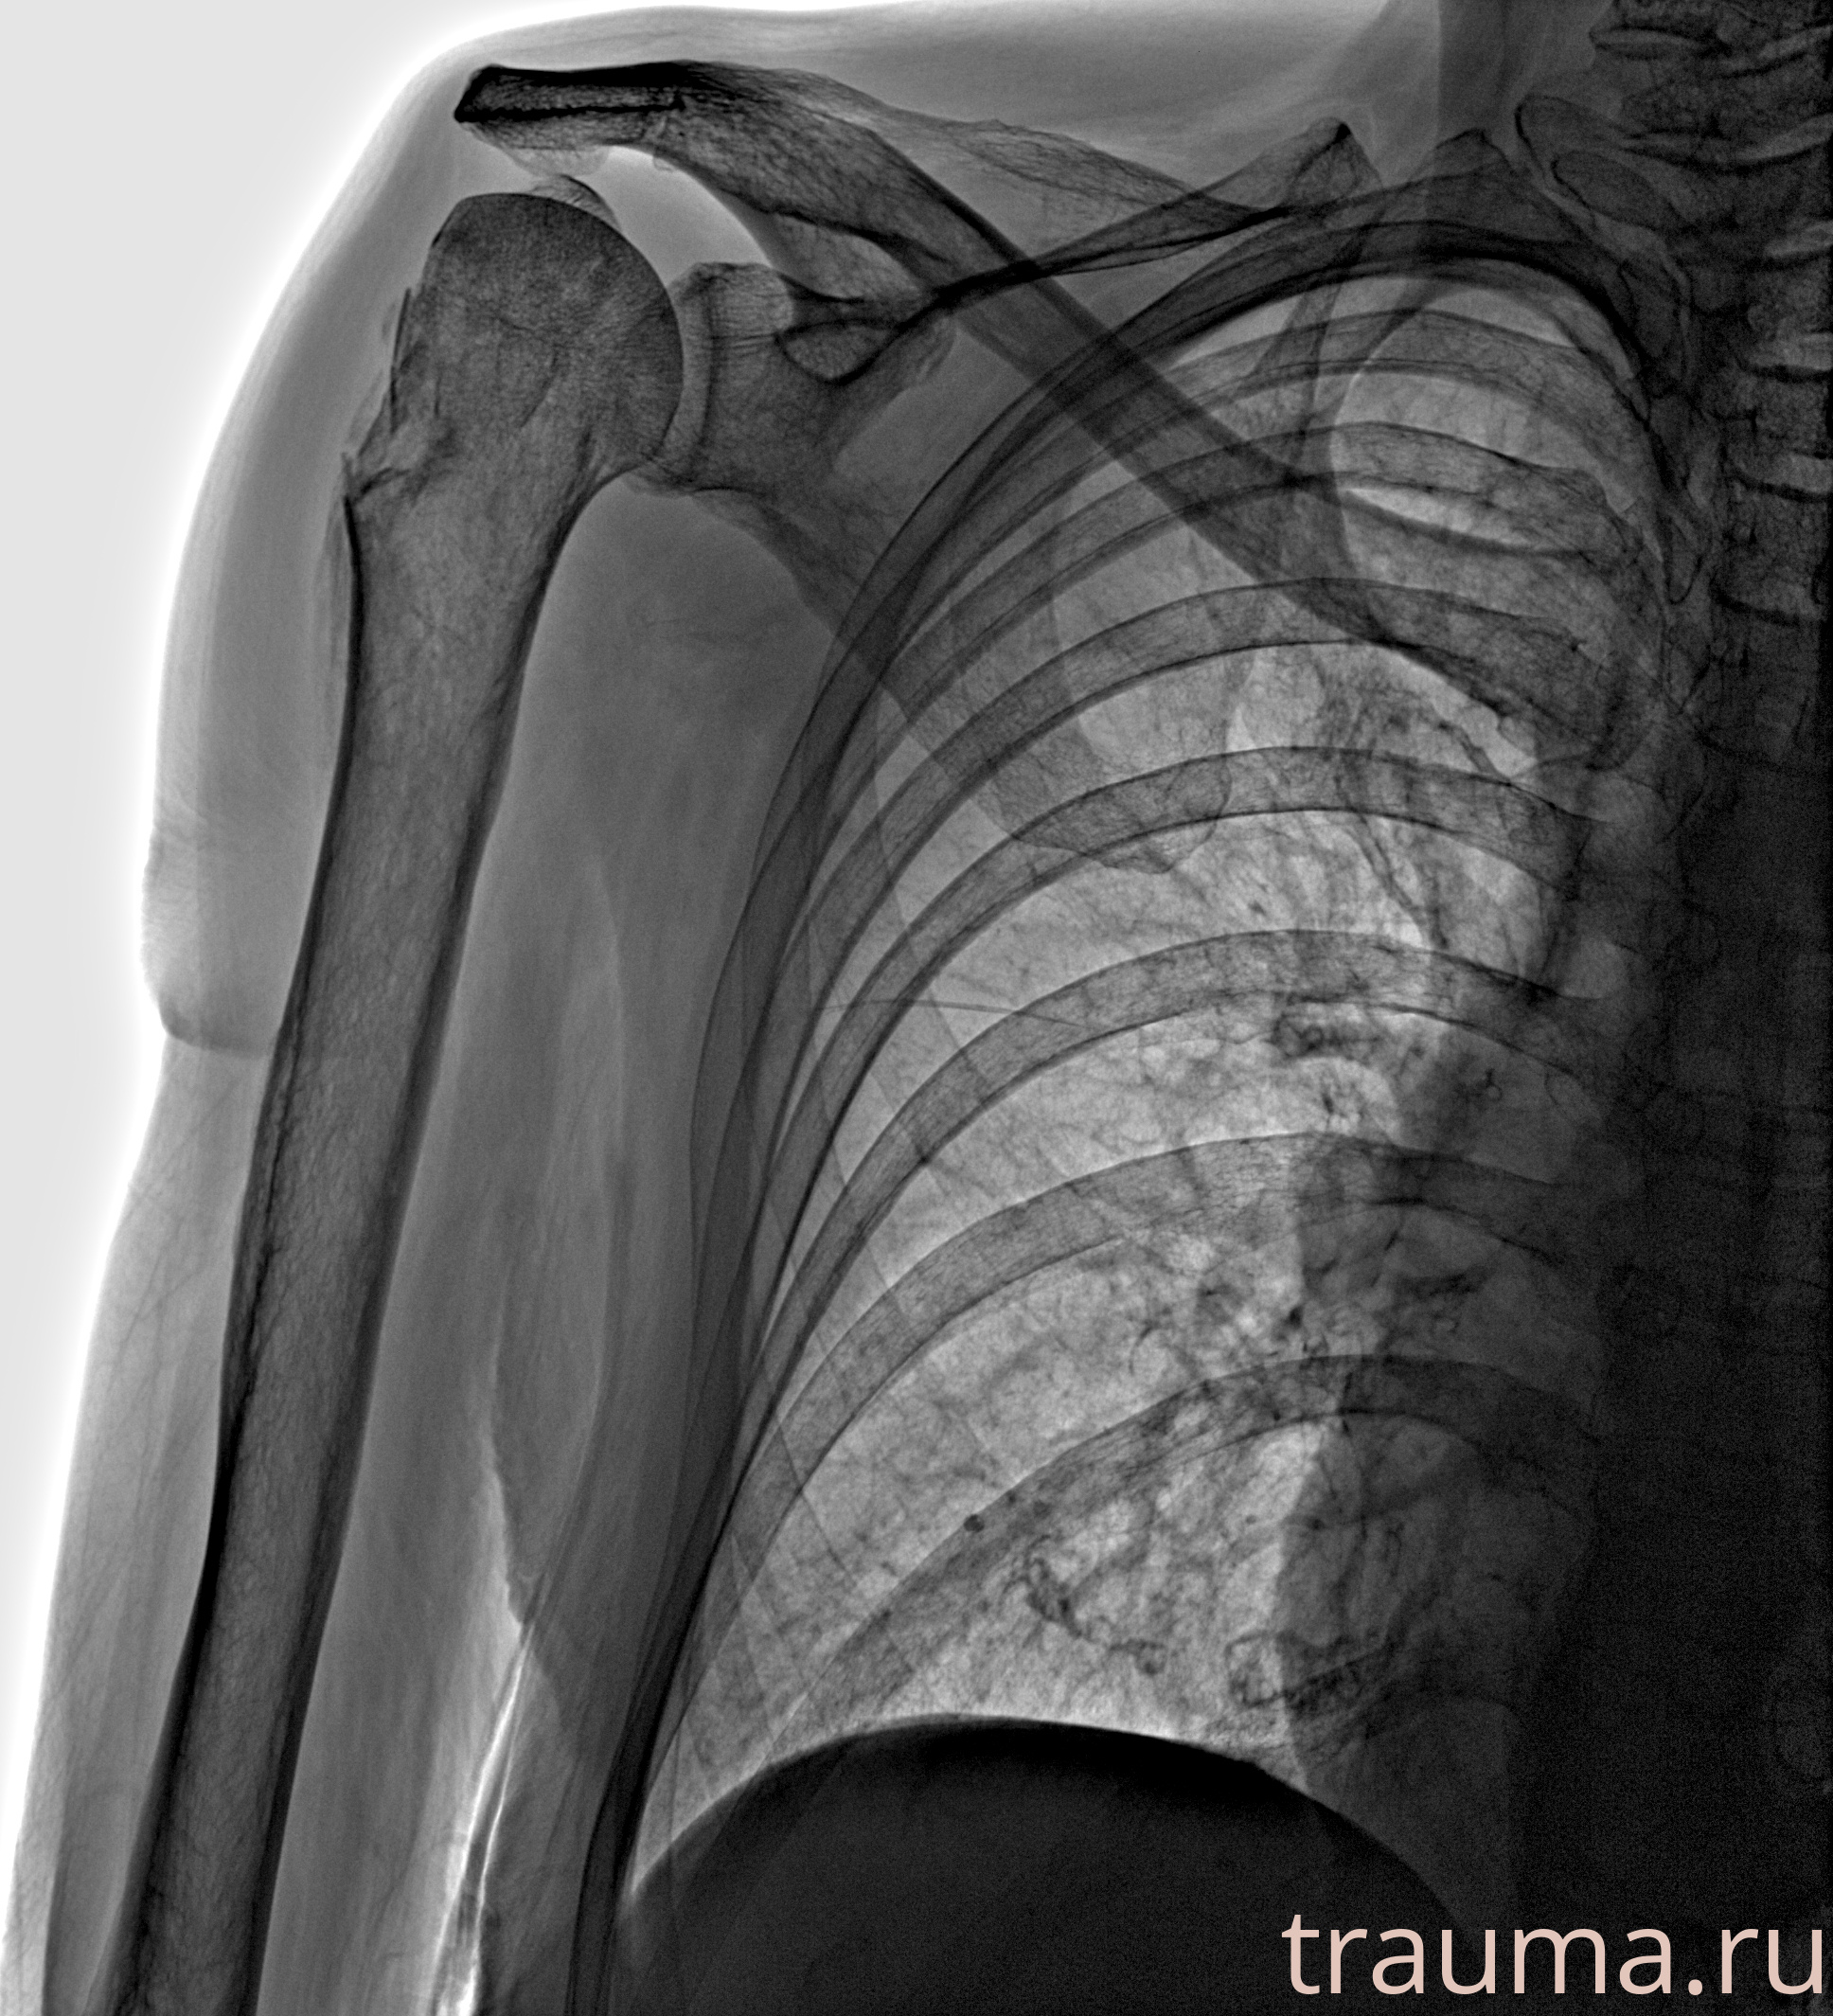

Рентгенограммы

Рентген на дому: по вашему адресу приезжает врач-рентгенолог, травматолог-ортопед с мобильным рентгеновским аппаратом, проводит диагностику травмы или заболевания, делает необходимые рентгенограммы, дает рекомендации по дальнейшему лечению. Получить качественные снимки в домашних условиях возможно благодаря уникальной методике, разработанной МосРентген Центром для института  Склифосовского